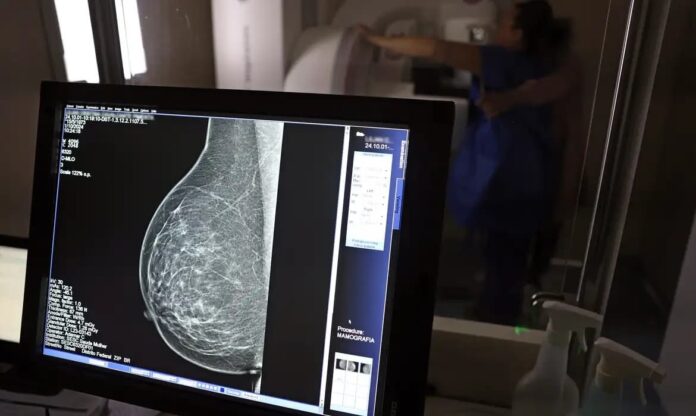

Essas informações reforçam a importância da campanha Outubro Rosa, que busca aumentar o acesso à informação e incentivar o diagnóstico precoce, especialmente através da mamografia, o principal método de detecção inicial da doença. O risco de mortalidade e a incidência da doença aumentam significativamente a partir dos 50 anos, tornando o rastreamento essencial nesta faixa etária.